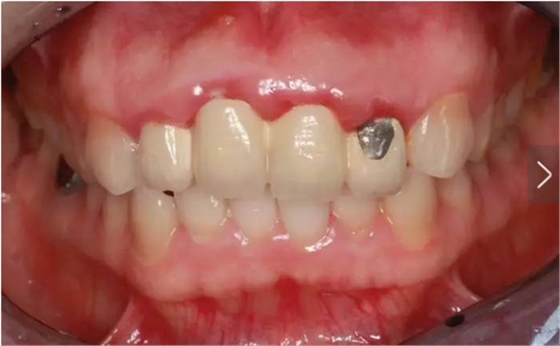

臨床檢查可見12~22烤瓷聯(lián)冠修復(fù),冠邊緣不密合,齦緣外形不協(xié)調(diào),牙齦紅腫,22烤瓷冠崩瓷。根管治療不完善,牙齦根尖部位有瘺管,X線影像顯示11、21根尖有陰影。上頜前突,上前牙修復(fù)體舌傾。 患者治療前口內(nèi)像 側(cè)位像 治療前曲面體層片 治療前前牙區(qū)X線片